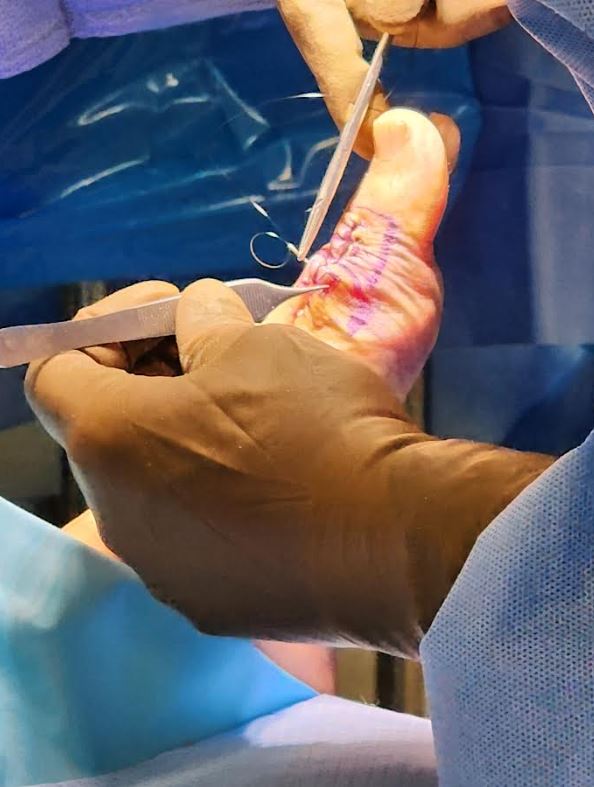

Hallux rigidus (arthritic great toe joint)

Hallux rigidus repair using the Regnauld technique, no metal or foreign body rejection. Immediate weight bearing and range of motion

Arthritic Joint Repair